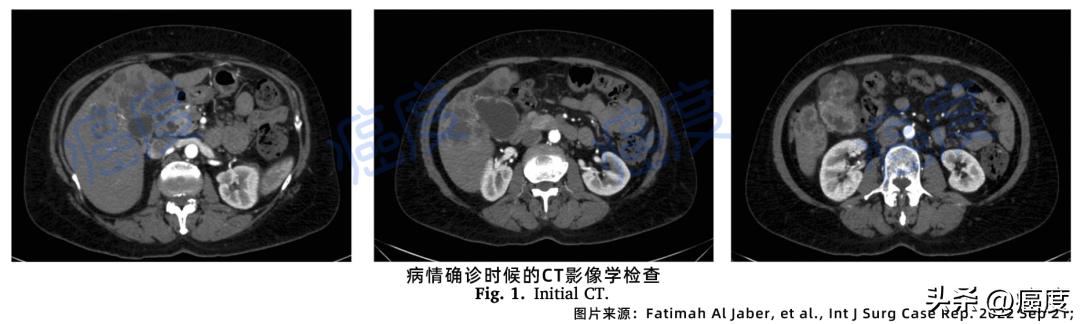

经过胸部、腹部和骨盆的CT扫描,确定为晚期胆囊癌伴随肝转移。远端的胆总管没有明确的阻塞性病变,腹部或盆腔没有明显的肿大淋巴结(如下图所示)。

图1. 病情确诊时候的影像学CT